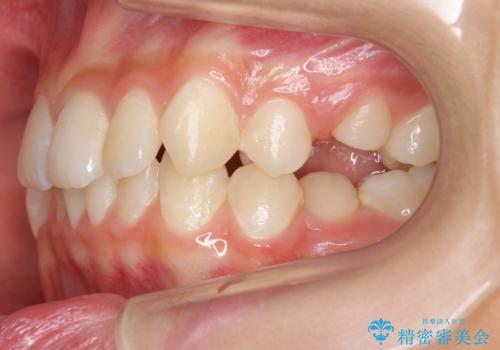

- 右上の犬歯が埋伏していたため、抜歯しました。

その後、右下の小臼歯を1本抜歯し、ワイヤー矯正を行いました。

犬歯の代わりに小臼歯を配列し、最小限の抜歯の本数としました。

犬歯の両側の歯に関しては移動することにより歯槽骨が順調に回復し、上顎洞底の形態にかかわらず歯根のパラレリングを行うことができました。

犬歯の両側の歯に関しては移動することにより歯槽骨が順調に回復し、上顎洞底の形態にかかわらず歯根のパラレリングを行うことができた理由としては、年齢が10代前半と若かったからだと思います。

成人ですと、なかなかこういった柔軟な歯の移動は難しいことが多いです。

左上4−7については、近心傾斜をしていたため、右上3を抜かずに遠心に移動して非抜歯で治療を行う案も提案しましたが、抜歯を選択されました。結果的に深く埋まっていた右上犬歯を牽引せずにすみ、さらに歯根の向きも整えることができてよかったです。治療も比較的短期間で済みました。